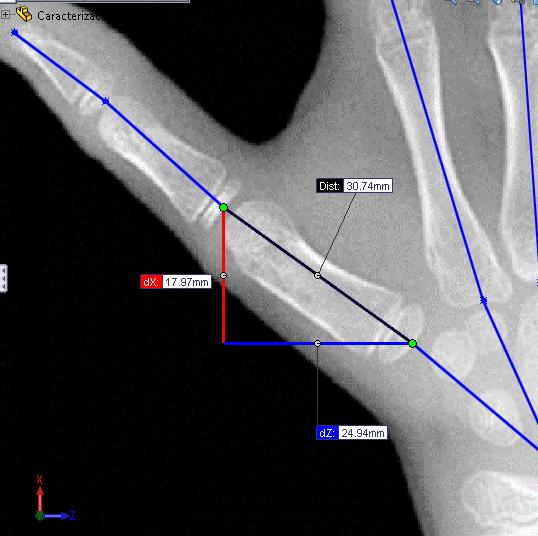

Figura 14. Toma de medidas de cada eslabón de las cadenas cinemáticas que componen la mano 26

Figura 15. Medición de ángulos entre eslabones de las cadenas cinemáticas que componen la mano

Una vez se tiene la representación esquemática de la mano humana planteada sobre el carpograma de referencia en un software CAD, es posible realizar mediciones, las cuales permiten conocer las dimensiones en milímetros de cada uno de los eslabones de las cadenas cinemáticas (Figura 14), así como también los ángulos de orientación de cada uno de ellos (Figura 15), los cuales posteriormente se analizarán en la determinación del modelo.

La totalidad de las mediciones realizadas sobre el carpograma de referencia se exponen en el ANEXO 2

Figura 14. Toma de medidas de cada eslabón de las cadenas cinemáticas que componen la mano

Fuente: (Gilsanz & Ratib, 2005); Edición: SolidWorks